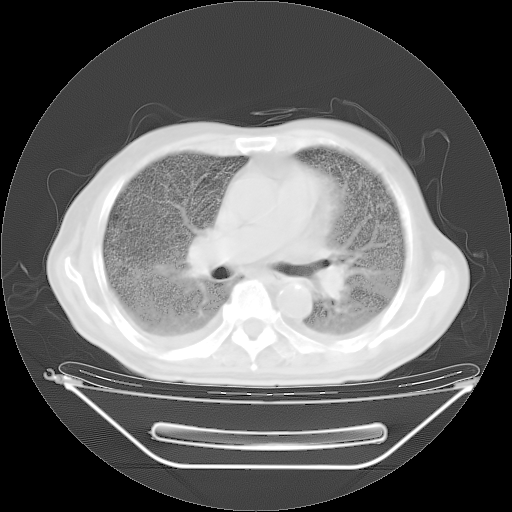

今天复查肺部CT,发现双肺广泛磨玻璃样改变。所以我把3月19日和5月9日相隔50天的肺部CT上传。请大家会诊。

2009年3月19日肺部CT片。

2009年3月19日肺部CT

5月9日肺部CT(在4月27日齐鲁医院肺部CT描述部分肺组织磨玻璃样改变,12天后肺组织广泛磨玻璃样改变)